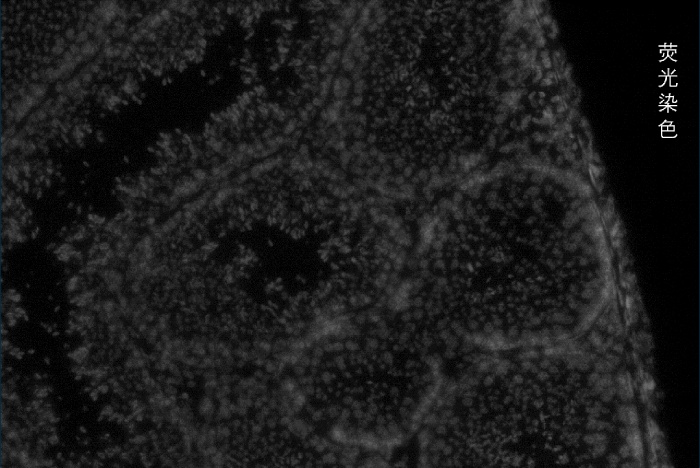

百創(chuàng)智造基于S系列空間芯片的底層設(shè)計(jì),可以得到完全沒(méi)有錯(cuò)誤的原片熒光圖像以及H&E圖像且與芯片完全對(duì)齊?;跓晒膺M(jìn)行細(xì)胞核的定位刻畫(huà)細(xì)胞核的邊界;基于HE的校準(zhǔn)輔助刻畫(huà)細(xì)胞的邊界,通過(guò)邊界信息映射到芯片上,提取相應(yīng)位置的測(cè)序數(shù)據(jù),實(shí)現(xiàn)精準(zhǔn)的單細(xì)胞分割。

2.原片熒光染色+原片H&E染色+原片空間測(cè)序相結(jié)合技術(shù):既可以進(jìn)行表達(dá)芯片H&E染色,又同時(shí)可以再表達(dá)芯片上進(jìn)行熒光染色,保證細(xì)胞分割更準(zhǔn)確。